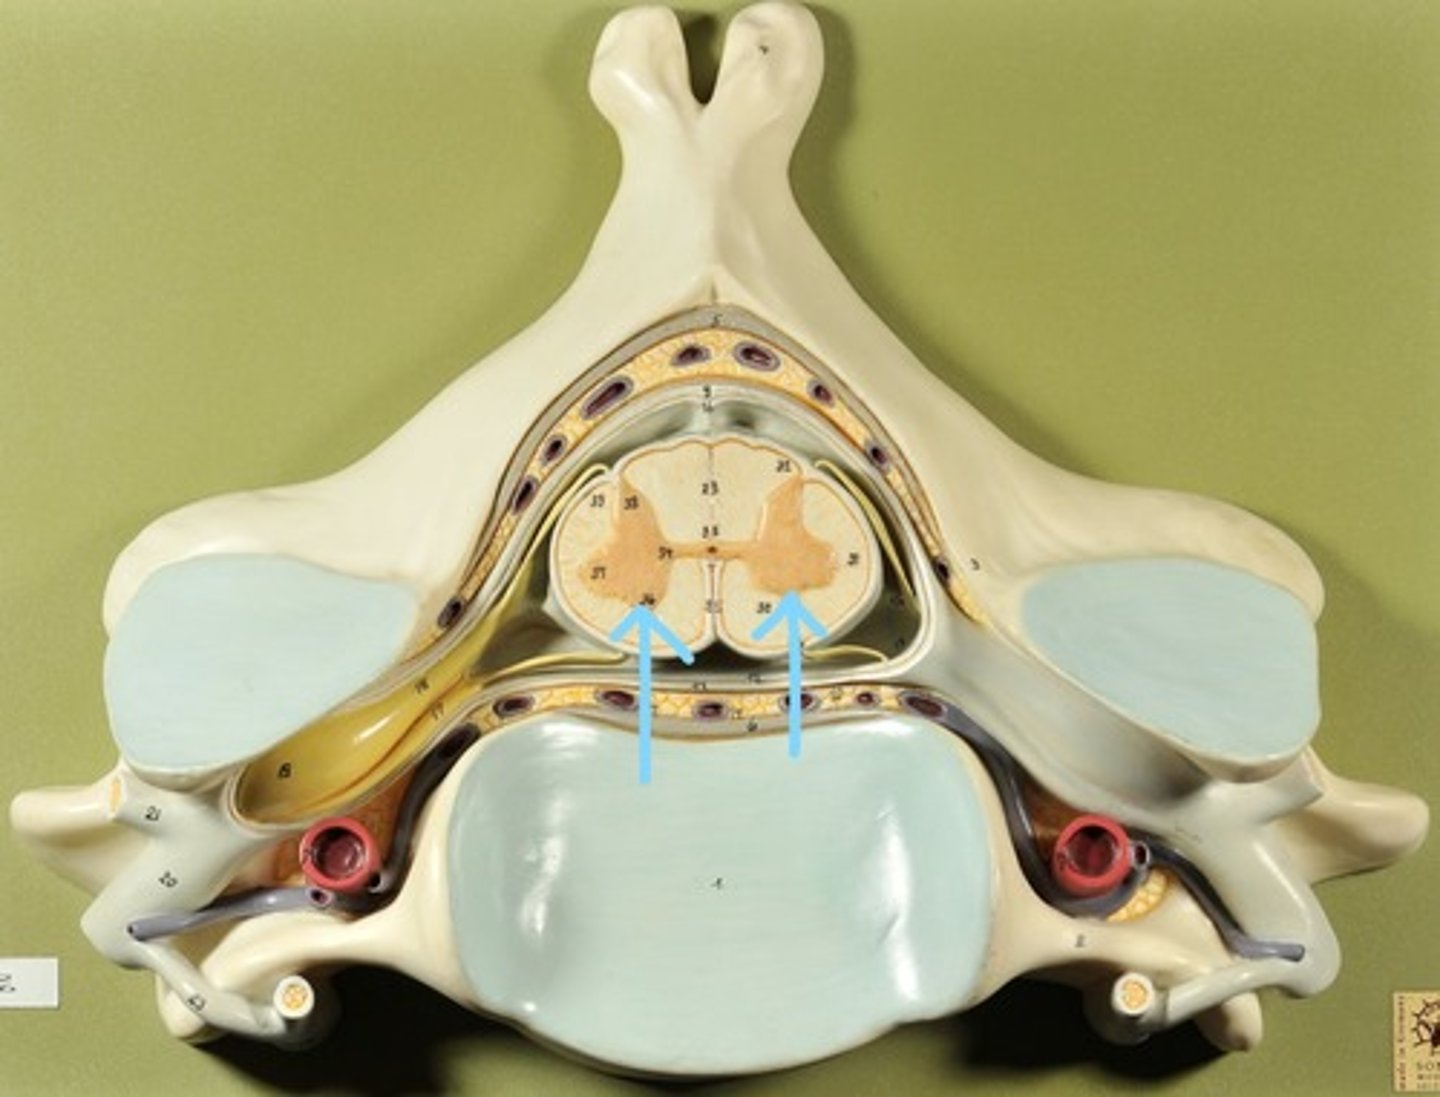

Identify all structures of spinal cord

White Matter of spinal cord

gray matter of spinal cord

Ventral Horns (gray matter)

Lateral Horns (gray matter)

Dorsal horns (gray matter)

Anterior Columns (white matter)

Lateral Columns (white matter)

Posterior Column (white matter)

central canal of spinal cord

Identify all structures

Pia Mater

Subarachnoid Space

Arachnoid mater

Subdural Space (brown line)

Dura mater

Epidural Space

Dorsal Root Ganglion

Dorsal Root

Ventral Root

Spinal Nerve